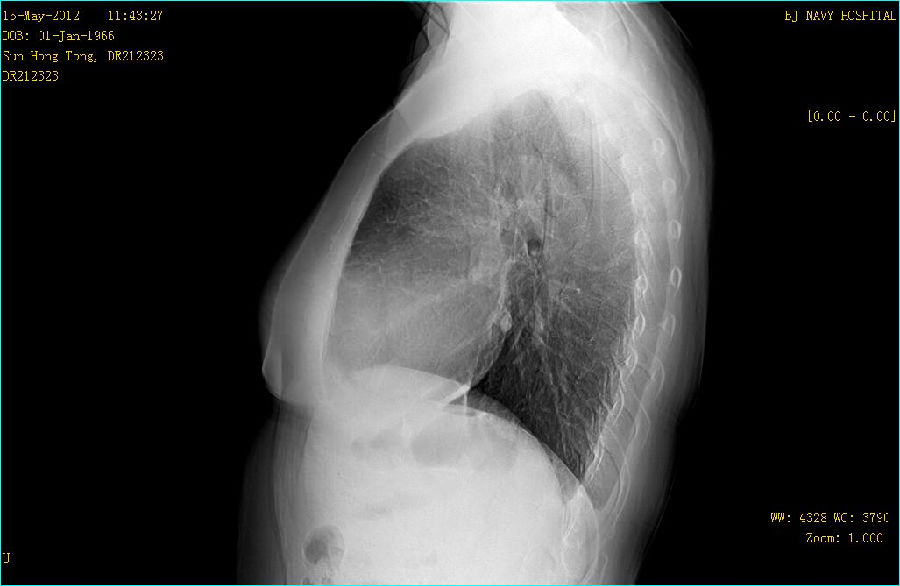

双能成像图片:

病例点评: GE公司的双能成像检查采用可以快速读取的X线平板探测器,由X射线球管间隔约150ms进行低能(低kVp)和高能(高kVp)两次曝光。采集到的图像经过图像工作站快速处理产生一组3幅图像:标准平面图像,软组织图像和骨骼(钙化)组织图像。这种双能量DR检查对于改善肋骨后面重叠区域的非钙化结节的能见度非常有效。同时对在肋骨间和超过骨组织钙化的结节能更好地显示。